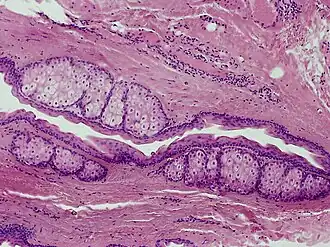

Description de l'image SkinTumors-P6260388.JPG.

Le stéatocystome multiplex est une affection congénitale bénigne autosomique dominante entraînant de multiples kystes sur le corps d'une personne. Le stéatocystome simplex est le pendant solitaire du stéatocystome multiplex[1].

On pense que les stéatocystomes proviennent d'une muqueuse anormale du canal sébacé.